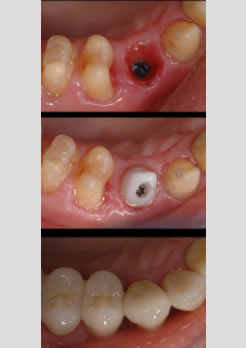

Antes – Paciente mulher 57 anos apresentou fratura do dente canino e foi realizado extração e instalação imediata do implante

Depois – Após 2 meses foi colocado o novo dente de porcelana com um pilar em zircônia (peça aparafuzada no implante)

Implante instalado //B- Abutment de zircônia // C-Coroa de porcelana finalizada

Coroas de porcelana finalizadas